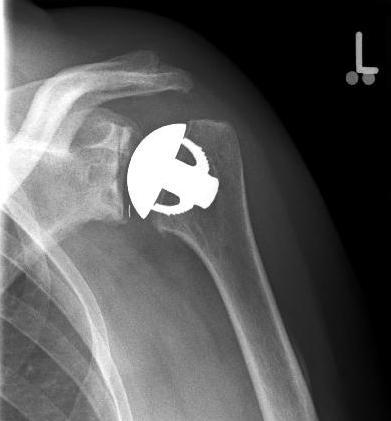

Special prostheses such as an inverse shoulder prosthesis (syn.: "Delta prosthesis", "Grammont prosthesis") for the combination of severe omarthrosis with joint instability and rotator cuff defects

Right: radiograph of an inverse shoulder prosthesis for rotator cuff defect arthropathy.

left: Inverted shoulder prosthesis (Aequalis reversed type, Tornier company).